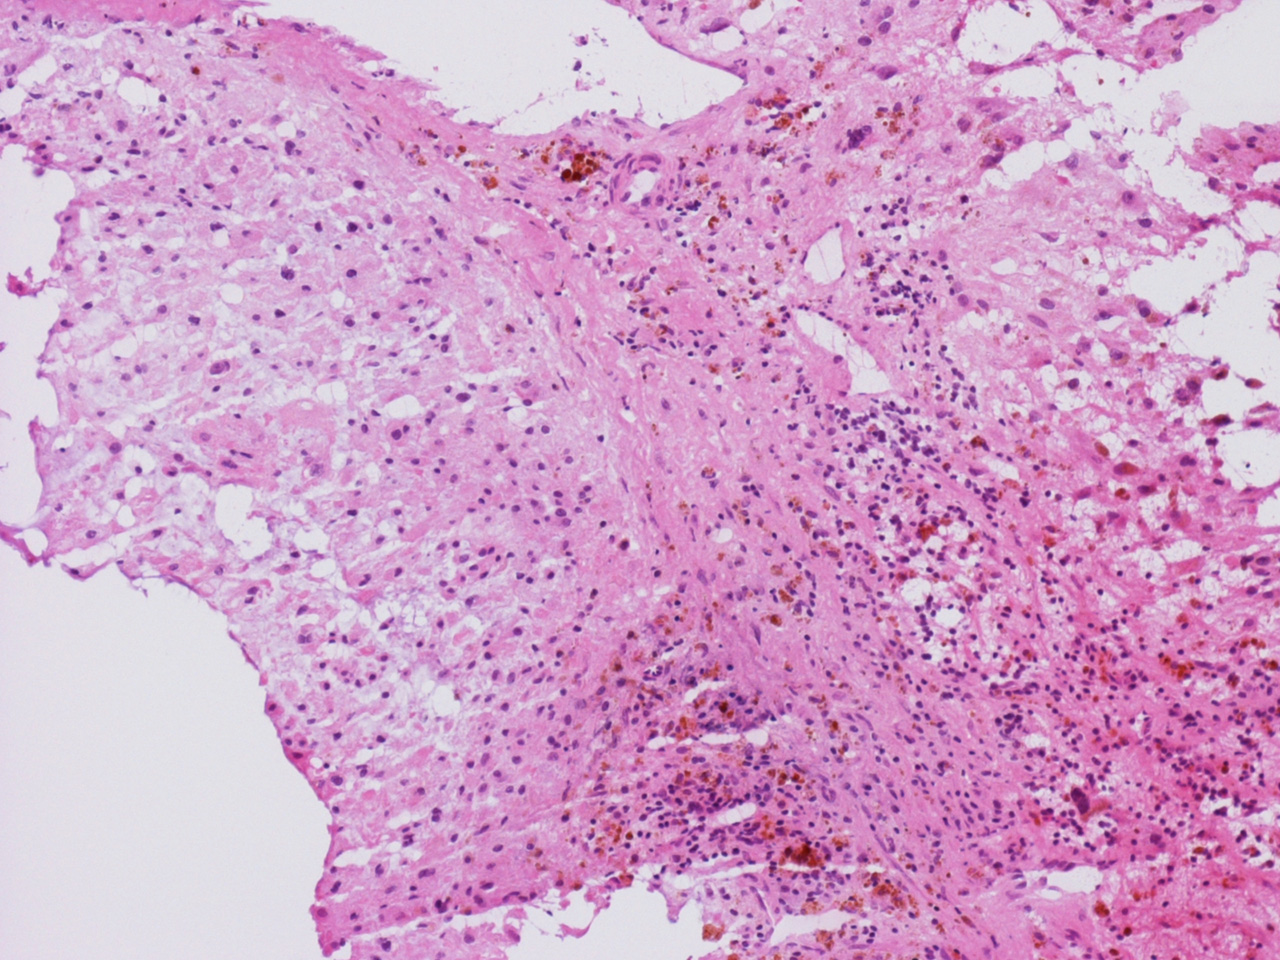

At the time of operation, a cytologic squash preparation (H&E) was prepared (Panels BC, and D). On low magnification, the lesion is composed of large clusters of eosinophilic cells with centrally located nuclei. There is some bluish acellular substance admixed with the tumor cells (Panel B). If you pay attention, some of the cells are arranged in short chains (arrows in Panel C). This is a frequently seen phenomenon in chordoma. On high magnification, the cells have centrally located medium sized to large, hyperchromatic nuclei. The cytoplasm is finely eosinophilic but not particularly bubbly  (Panel D). The frozen sections (Panels E and Freflect the cytologic features. The tumor is composed of solid sheets of large tumor cells admixed with small amount of fibrous areas, mild chronic inflammatory cell infiltration and hemosiderin depositions (Panel E). On high magnification, the tumor cells are admixed with bluish extracellular material.  The cytoplasm is coarsely granular with fine bubbles. The permanent sections (Panel G and Hshow similar features. And the bubbly cytoplasm is more prominent in the permanent sections (Panel H). Focal bone invasion is present (Panel I). The cytoplasmic vacuoles are best appreciated in the semithin section (Panel M). Results of special studies are as follows:

The characteristic histologic findings in chordomas are large polygonal cells with distinct cell membrane and the vacuolated physaliphorous cytoplasm, the term deriving from the Greek physalis, or "bubble. The vacuolated or physaliphorous cells are best appreciated in cytologic smears or squash preparations. Tumor cells grow in small nests and cords within a myxoid/chondroid matrix and demonstrate round, sometimes rather uniform nuclei with low nuclear-to-cytoplasmic ratios. The tumor cells tend to adhere into clusters and cords. The classic large physaliphorous cell has a centrally located nucleus surrounded by a narrow rim of cytoplasm that in turn, is encircled by a ring of more peripherally located cytoplasmic vacuoles. Nuclear grade is not particularly high in some cases but many of them have clearly recognizable nuclear pleomorphism. Occasional large, atypical cells are present. These nuclear changes should not be present in benign notochordal cell tumor and ecchordosis physaliphora/fetal vestige [Amer & Hameed, 2010]